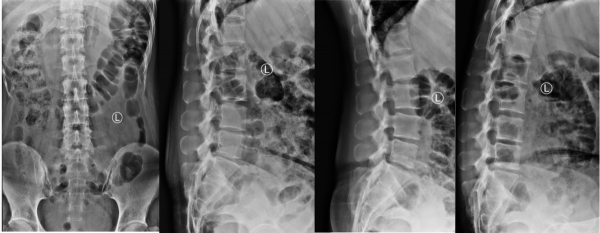

王作偉主任接診後,瞭解了小劉的情況,再根據各項影像學檢查以及詳細查體後,確診她為腰椎間盤突出症(腰4/5、腰5骶1)。王作偉主任表示:從患者的影像學片子上看,可以非常明顯地看到腰4/5、腰5骶1兩個節段的突出,而且已經嚴重的擠壓到後方椎管裡的神經,需要考慮儘快手術減壓。根據患者的病情,又考慮到患者今後還要進行長期訓練以及治療後恢復問題,建議她進行椎間孔鏡手術微創治療。

術前影像學資料: